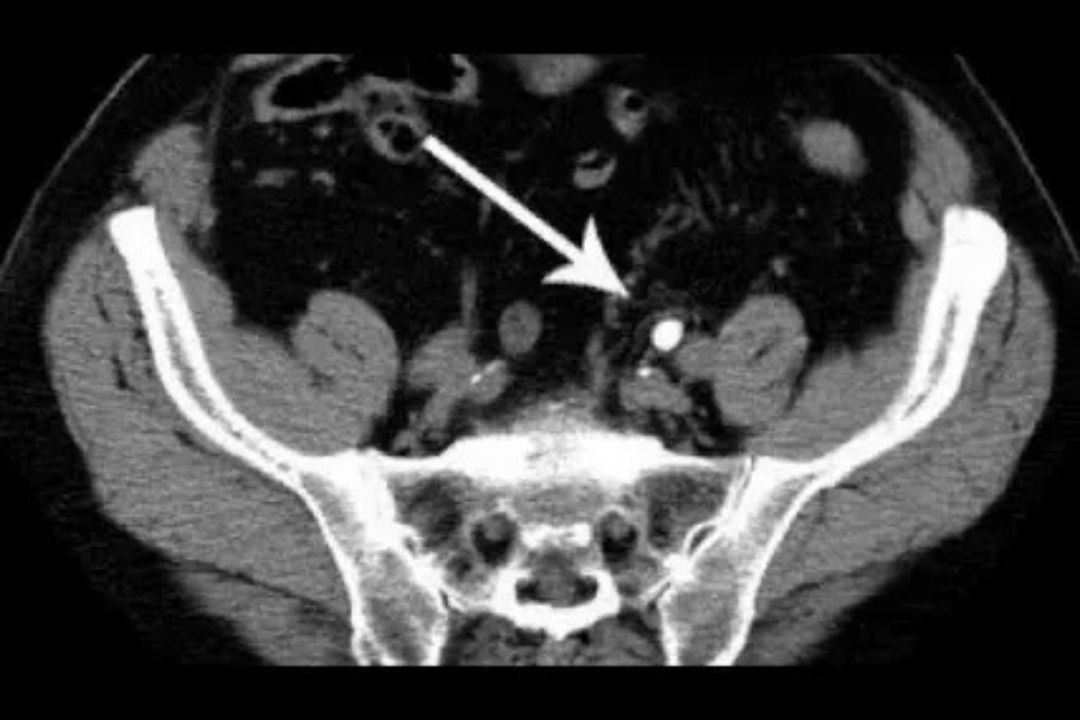

A CT (Computed Tomography) scan of the breast is a non-invasive imaging test that uses X-rays to create detailed, cross-sectional images of breast tissue. Unlike standard CT scans, low-radiation breast CT utilizes advanced technology and optimized protocols to minimize radiation exposure while maintaining high image quality. This approach offers a 3D view of the breasts, allowing radiologists to detect abnormalities such as tumors, cysts, or calcifications with precision.

2. Accuracy in Dense Breast Tissue: Nearly 40–50% of women have dense breast tissue, which can mask tumors on a mammogram. CT scans offer better visualization in such cases.

1. Superior Imaging: Offers 3D, high-resolution images for accurate diagnosis.